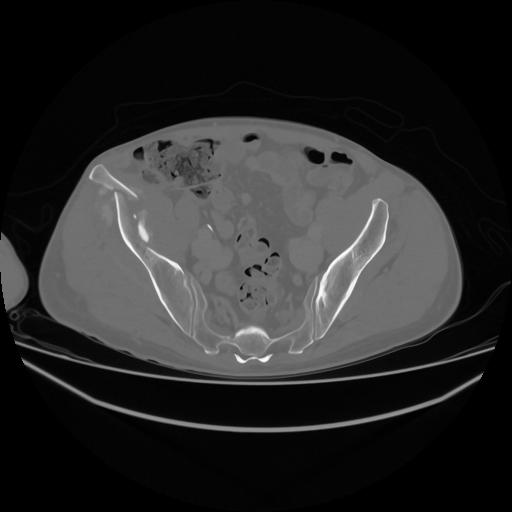

5 CUERPO,CE,Vol,1.0,CUERPO,,